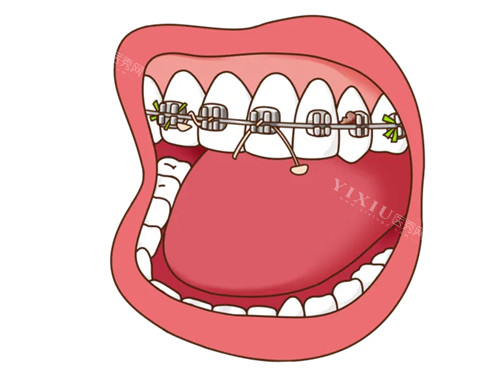

沈阳奥新口腔在牙齿矫正技术方面投入了大量资源。医院配备了智能化设备,如德国X-Guide三维导航种植系统和意大利NewTom锥形束CT。这些设备能够为医生提供更精细的诊断和治疗方案,提高矫正的成功概率和舒适度。例如,iTero口扫仪可以在5分钟内生成牙齿移动动画,预测矫正周期。